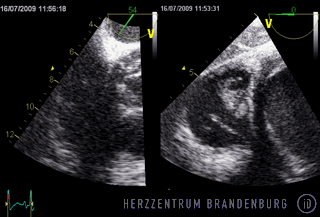

Im Rahmen der Behandlung ist es zunächst wichtig festzustellen wie ausgedehnt eine Infektion fortgeschritten ist. In der Regel ist dazu eine transösophageale Echokardiographie notwendig, um das Ausmaß und die Größe von Vegetationen festzustellen und eine eventuelle Klappenmitbeteiligung einschätzen zu können. Das weitere Vorgehen muss danach individuell, meist in enger Kooperation zwischen interventioneller Kardiologie und Herzchirurgie festgelegt werden.